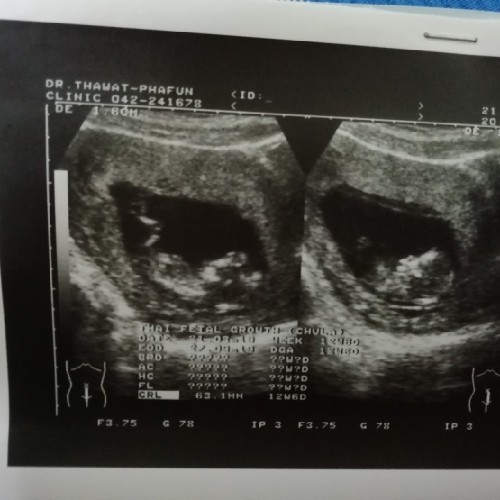

12 week ค่ะ เพิ่งซาวน์เมื่อวานนี่เอง 😊

12วีคจ้า ปัจจุบัน25วีคแล้วค่ะ💕